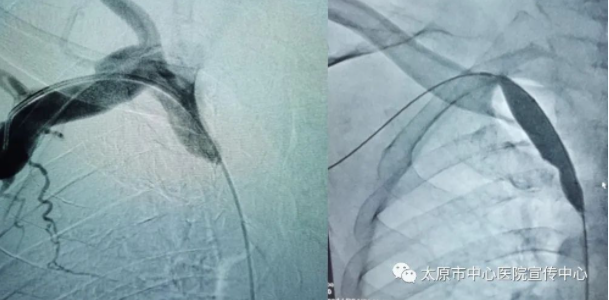

2月21日,在醫(yī)院導(dǎo)管室的配合下,科室專家為郭大爺成功實(shí)施中心靜脈造影術(shù)、球囊擴(kuò)張術(shù)及植入支架術(shù)。術(shù)后,郭大爺右側(cè)手臂腫脹明顯減輕,頭暈、胸憋、氣緊等癥狀也有了明顯的好轉(zhuǎn)。此項(xiàng)技術(shù)填補(bǔ)了太原市中心醫(yī)院血液透析血管通路領(lǐng)域的空白,為中心靜脈反復(fù)狹窄,行球囊擴(kuò)張手術(shù)效果不佳的患者帶來福音。